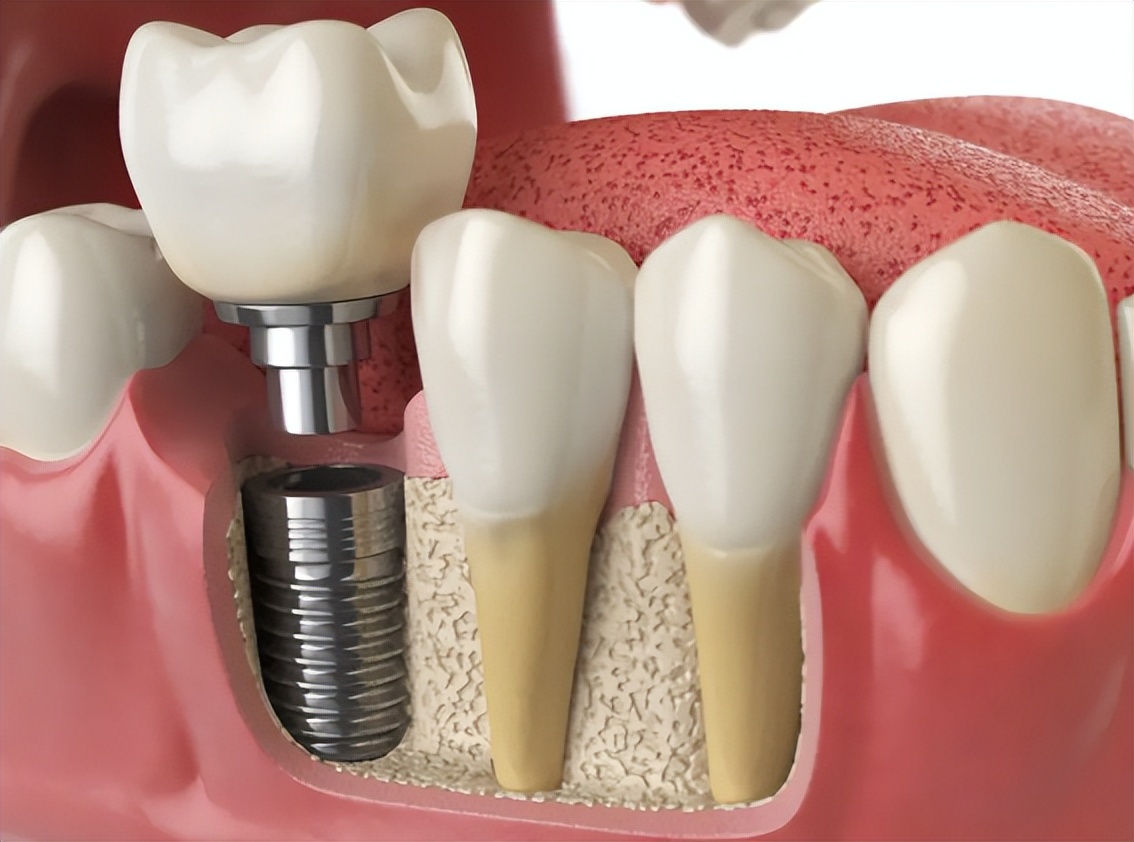

再等两周,牙龈长好了,就可以根据之前你的整个牙周拍摄的片子,来制作一个可以和周围牙齿紧密吻合的牙齿模型,那个让你钱包一次大出血的东西——牙冠。

现在的牙冠大多是全瓷的,硬度堪比金刚石,颜色白得像抛过光的盥洗台。但我必须告诉你一个小秘密:这颗牙冠,和你嘴里的螺丝并不是焊死的,它们是通过一颗极小的、极精密的中央螺丝连接的。

当医生把这颗牙冠戴入你口中,拧紧最后一道螺丝,再用树脂封上孔洞后,恭喜你,口腔里的房地产项目也就可以交付业主了。